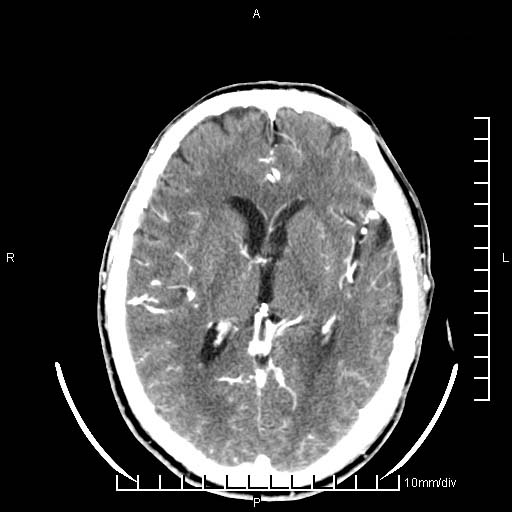

临床以双下肢浮肿,疼痛收治,无明显神经系统症状,既往无梗塞,出血病史。左颞叶见低密度灶,考虑什么?

无强化、 无占位、局部脑沟增宽, 软化灶吧。